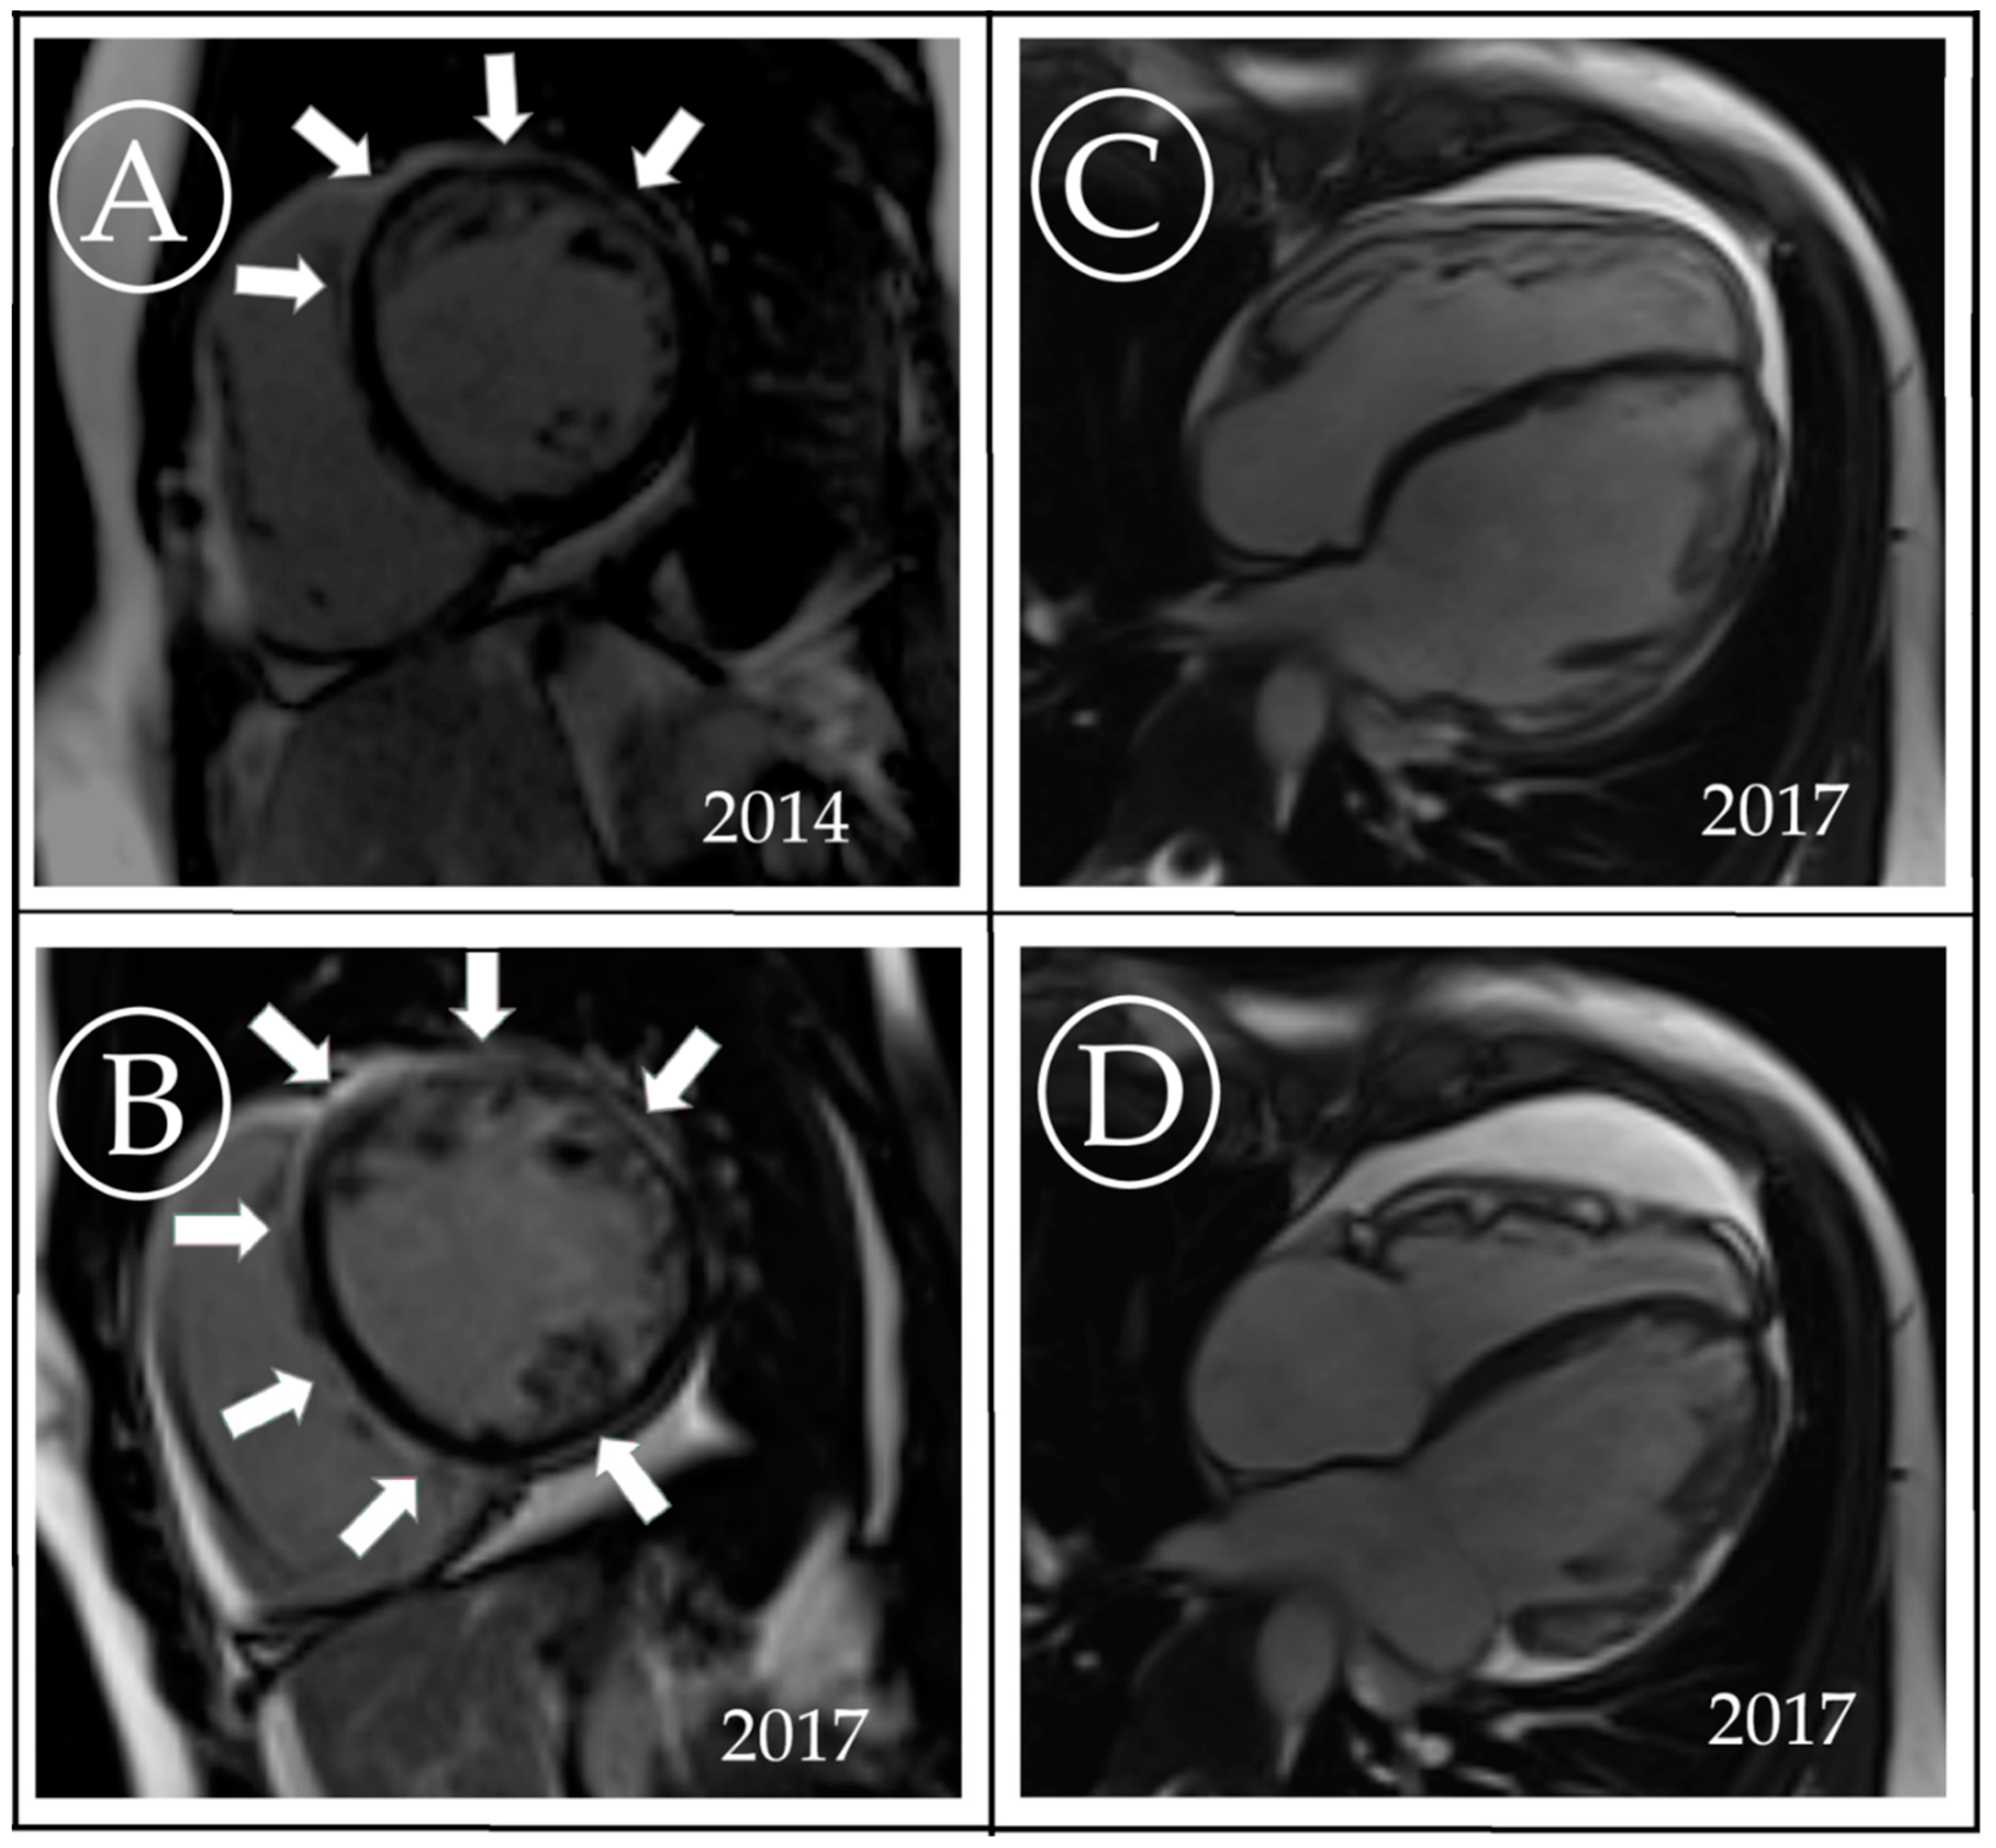

3. Case Description